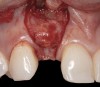

Problem: The implant is placed too facially, and there is significant labial gingival recession, contour change, and mucosal discoloration around the implant, abutment, and crown (Figure 3 and Figure 4). The implant attachment apparatus is intact and healthy, but the patient has a thin periodontal phenotype.

The following case report provides an example of this case scenario: A 28-year-old white female patient presented with her maxillary right lateral incisor significantly longer than the contralateral tooth following restoration of an existing crown that was 10 years old (Figure 3). The patient was dissatisfied with the esthetic appearance of the restoration due to the increased length, recession of the gingival tissues, and discoloration of the surrounding mucosa (Figure 4). Similar to case scenario No. 1, the first step in treatment was to decoronate the healthy implant by placing a flat surgical cover screw and employing a provisional resin-bonded-retained (RBR) prosthesis as a transitional fixed restoration (Figure 5 and Figure 6). The gingival augmentation in situ was allowed to take place for 2 to 3 weeks and was evaluated after that time (Figure 7).

Fig 4. Intraoral view of tooth No. 7 with the gingival zenith more apical than the adjacent central incisor and canine tooth.